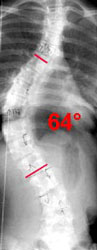

На рисунках слева размещены фотографии внешнего вида и рентгенограммы пациентки до и после хирургического лечения, что до недавнего времени позволяло судить

о эффективности операции. Основным количественным критерием при этом была величина коррекции деформации позвоночника по углу Кобба,

а по фотографиям хирург мог судить о косметическом эффекте операции, т.е. наиболее значимый для больного

фактор улучшения внешнего вида оценивался субъективно и лишь на качественном уровне.

Интегральный индекс PTI дает количественную оценку внешнего вида пациента в сопоставлении с гармоничной формой туловища. В приведенном примере пациентка имела PTI равный 2,8

(соответствует выраженным нарушениям формы туловища), а после операции - 1,7 (соответствует умеренным отклонениям формы туловища), таким образом коррекция по PTI

составила 39%, что соответствует среднестатистическому результату оперативного лечения с ипользованием CDI инструментария.

1 год после операции: угол по Коббу 23° (-64%), PTI=1,7 (-39%)